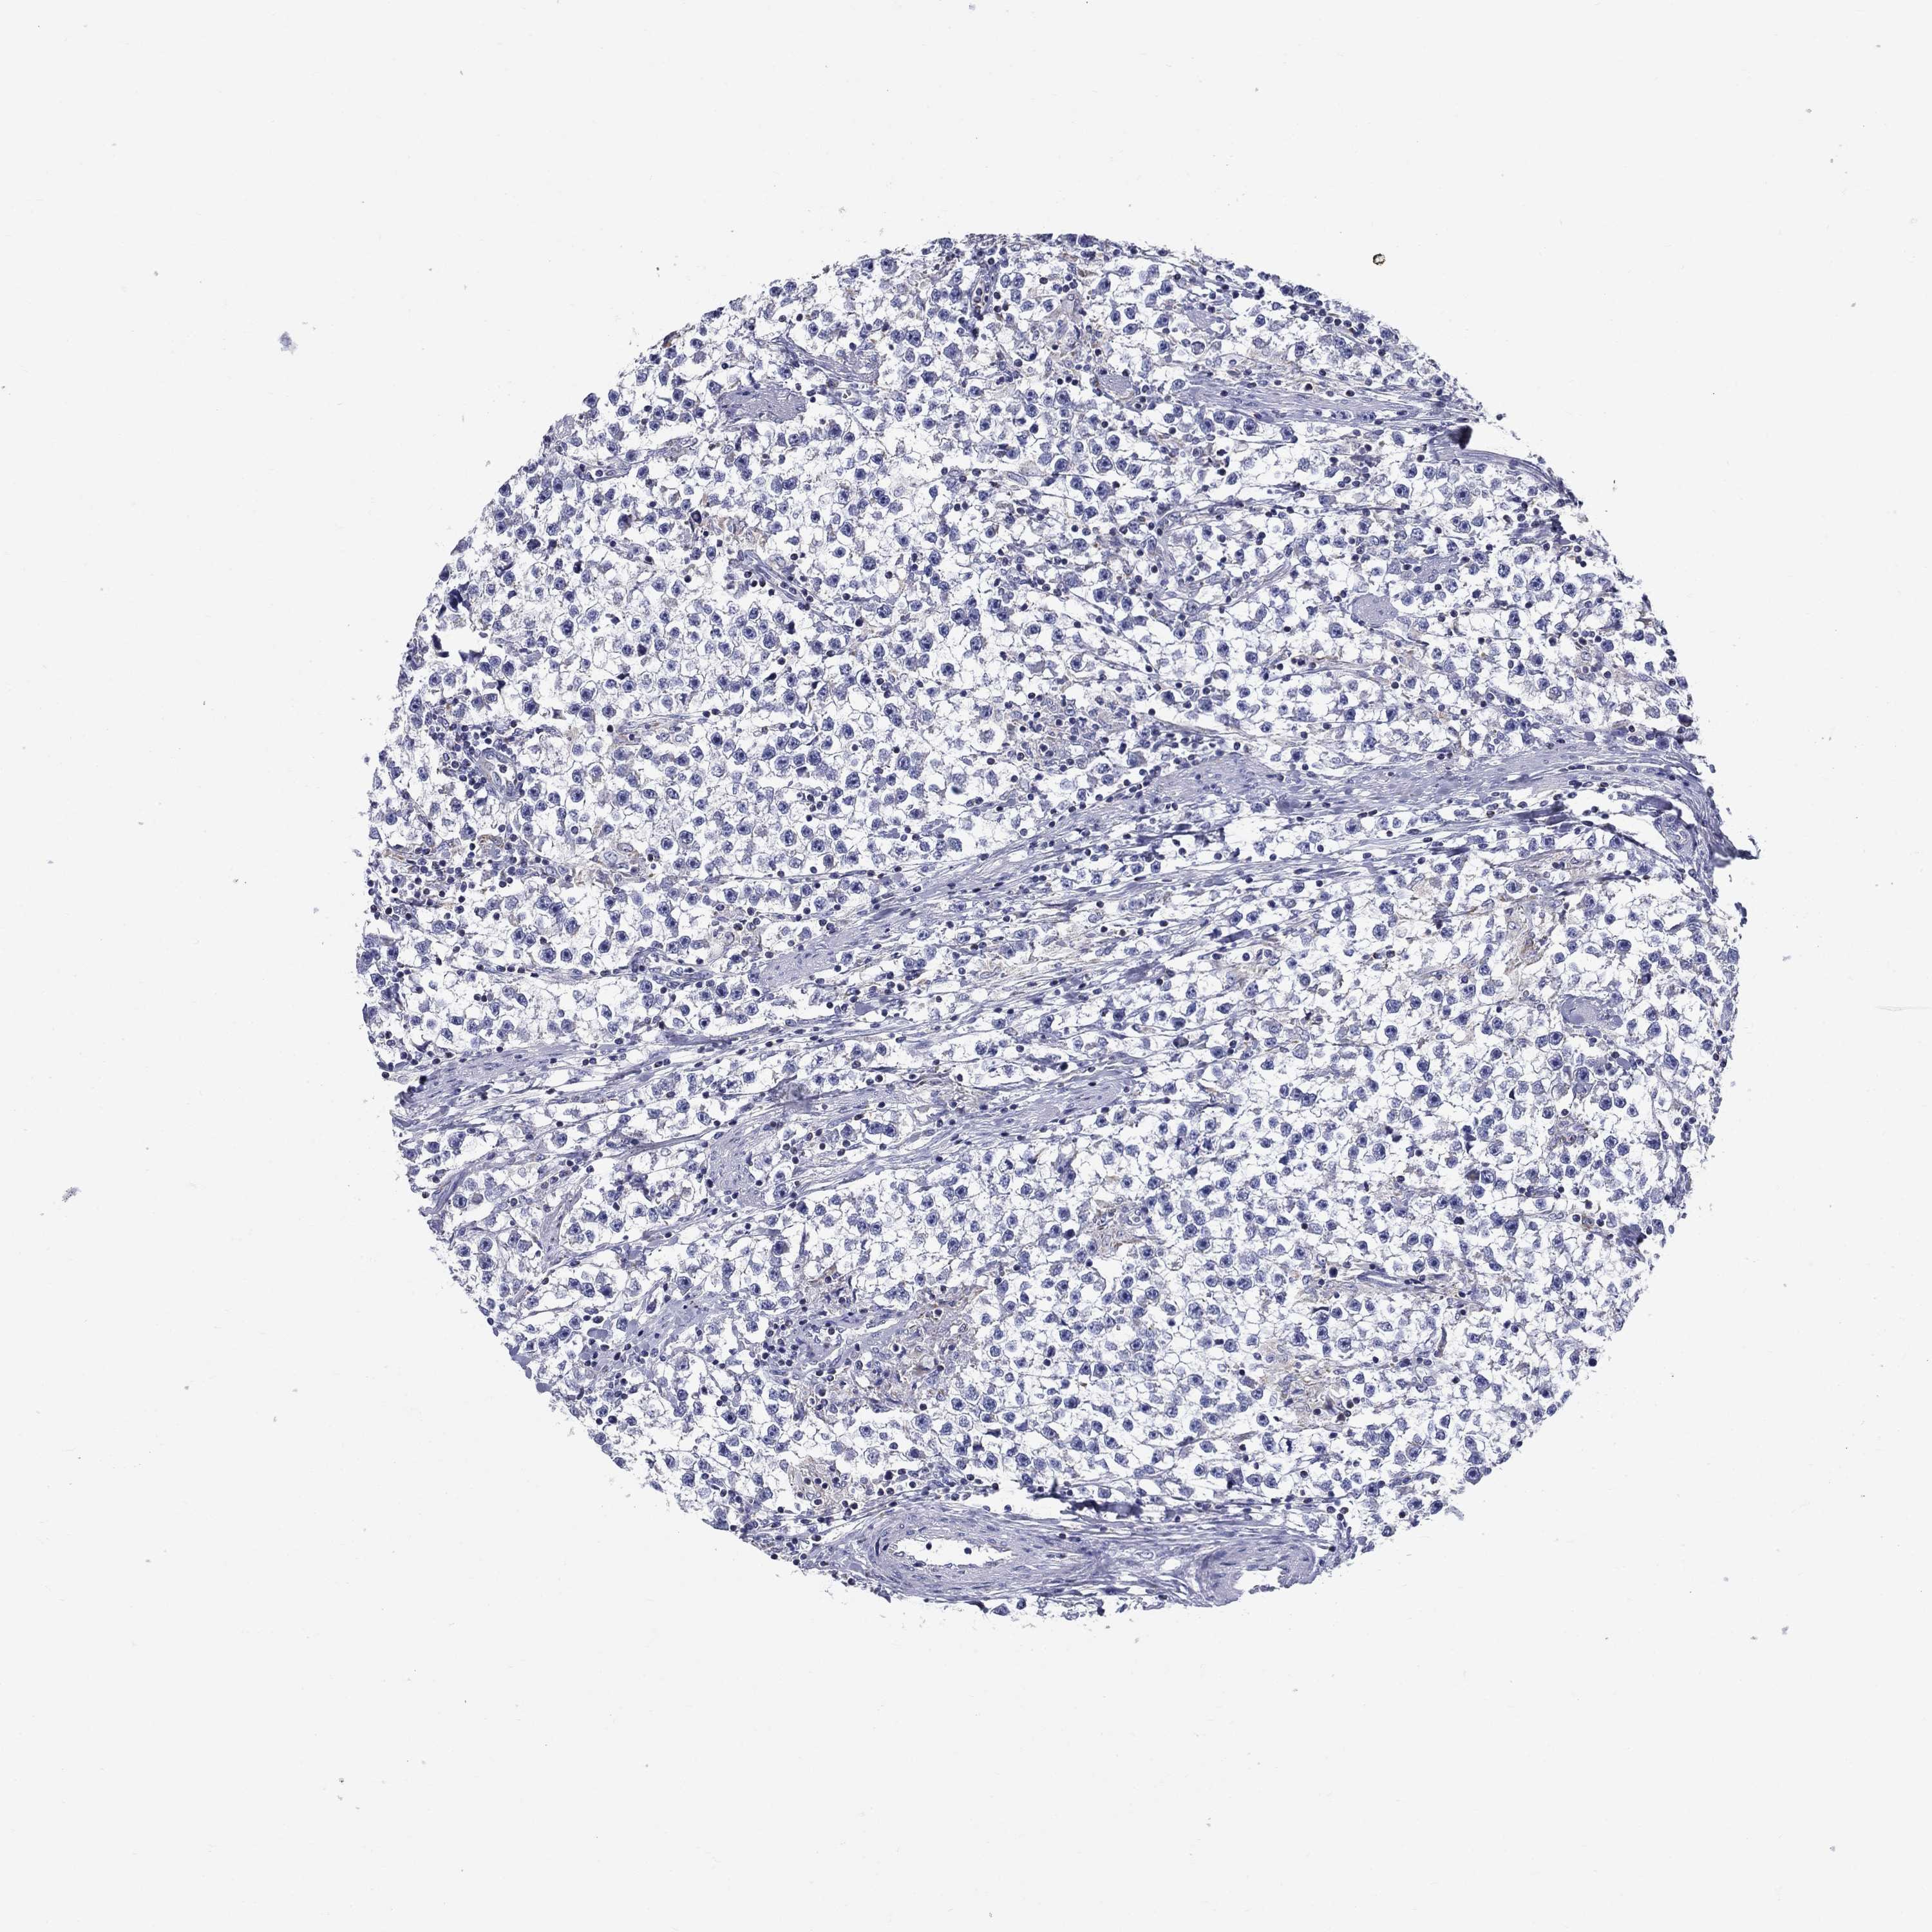

TESTIS CANCER - Protein expressioni

A mouse-over function shows sample information and annotation data. Click on an image to view it in a full screen mode. Samples can be filtered based on level of antibody staining by selecting one or several of the following categories: high, medium, low and not detected. The assay and annotation is described here.

Note that samples used for immunohistochemistry by the Human Protein Atlas do not correspond to samples in the TCGA dataset.

Antibody stainingi

Antibody staining in the annotated cell types in the current human tissue is reported as not detected, low, medium, or high, based on conventional immunohistochemistry profiling in selected tissues. This score is based on the combination of the staining intensity and fraction of stained cells.

Each image is clickable and will lead to virtual microscopy that enables deeper exploration of all samples and also displays staining intensity scores, fraction scores and subcellular localization as well as patient and tissue information for each sample.

Antibody HPA076321

Seminoma, NOS

Carcinoma, Embryonal, NOS